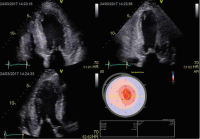

Abbildung 9: Links: Auf den rechten Ventrikel fokussierter apikaler 4-Kammer-Blick. ROI im Bereich des rechten Ventrikels (freie Wand und interventrikuläres Septum). Angezeigt werden links oben der globale Strain des rechten Ventrikels (–21,6 %), der globale rechtsventrikuläre Strain der freien Wand (–26,6 %) sowie automatisch auch die TAPSE (20 mm). Links unten werden die segmentalen rechtsventrikulären Strainwerte angezeigt. Rechts oben: Die Strainkurven aller rechtsventrikulärer Segmente (synchroner Kontraktionsablauf).

Keywords: EchoKardiologiestrain